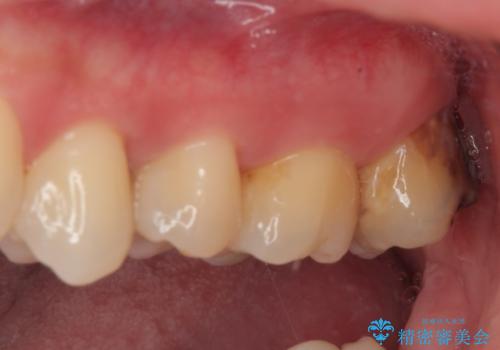

セラミッククラウンの適合はレントゲン写真からも分かる通り、境界がぴったりと合った、高適合のものとなりました。

矯正治療により処置が可能な位置に歯が移動したため、オールセラミッククラウンにて補綴治療を行うこととしました。